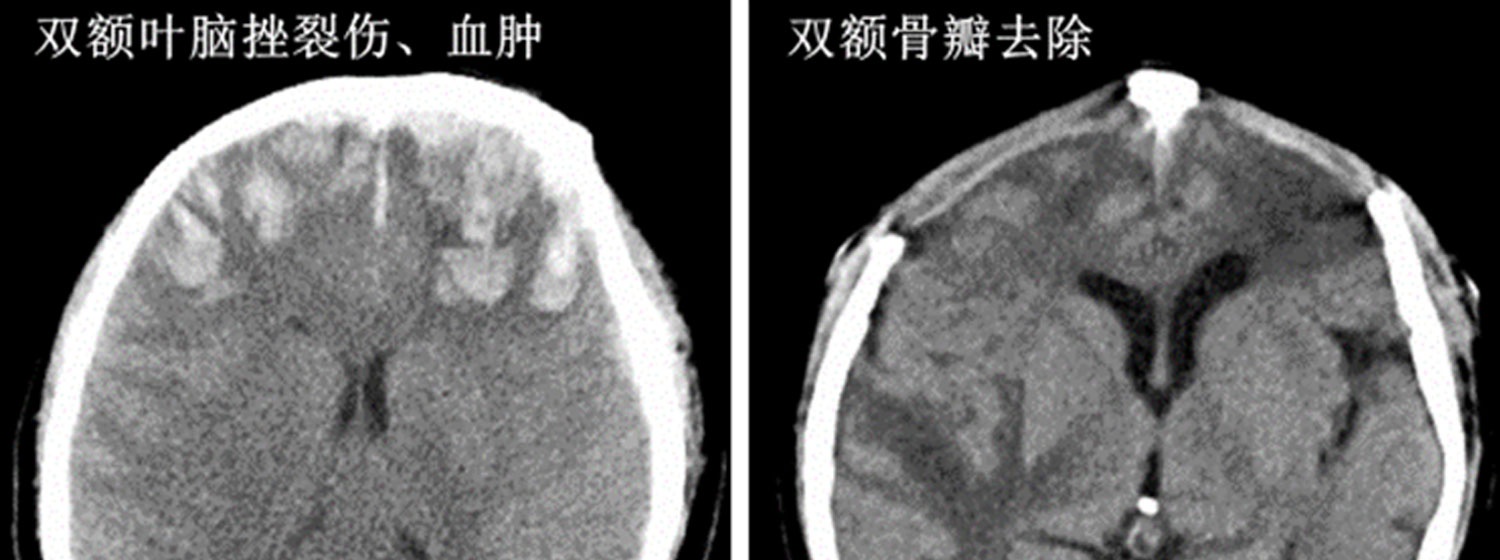

颅脑外伤,脑出血,脑肿瘤,脑梗塞等是常见的脑部疾患……